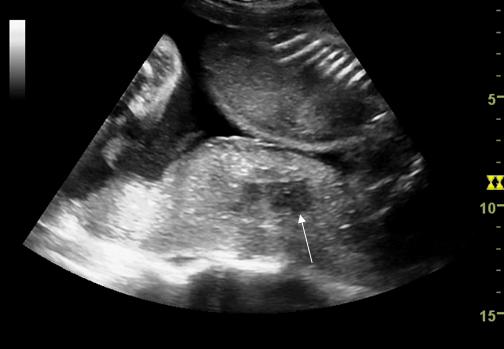

Abruptio placentae (DPPNI)

Prematura separare a unei placente normal inserate de miometru este o cauza majora de morbiditate si mortalitate materna si perinatala. Incidenta in trimestrul III este de 0,5 - 1,3%, cu mortalitate perinatala de 15 - 70%.[1,9,14]

Diagnosticul este de obicei clinic: sangerare, travaliu prematur, durere, panica, cresterea tonusului uterin bazal,tahicardie ; ecografic se evidentiaza placenta detasata in diferite grade, cu o zona hipoecogena in crestere retroplacentar.

Fig. nr. 223. Hematom retroplacentar ( sageata )relativ recent, hipoecogen ,la o sarcina de 30 sapt. cu DPPNI.